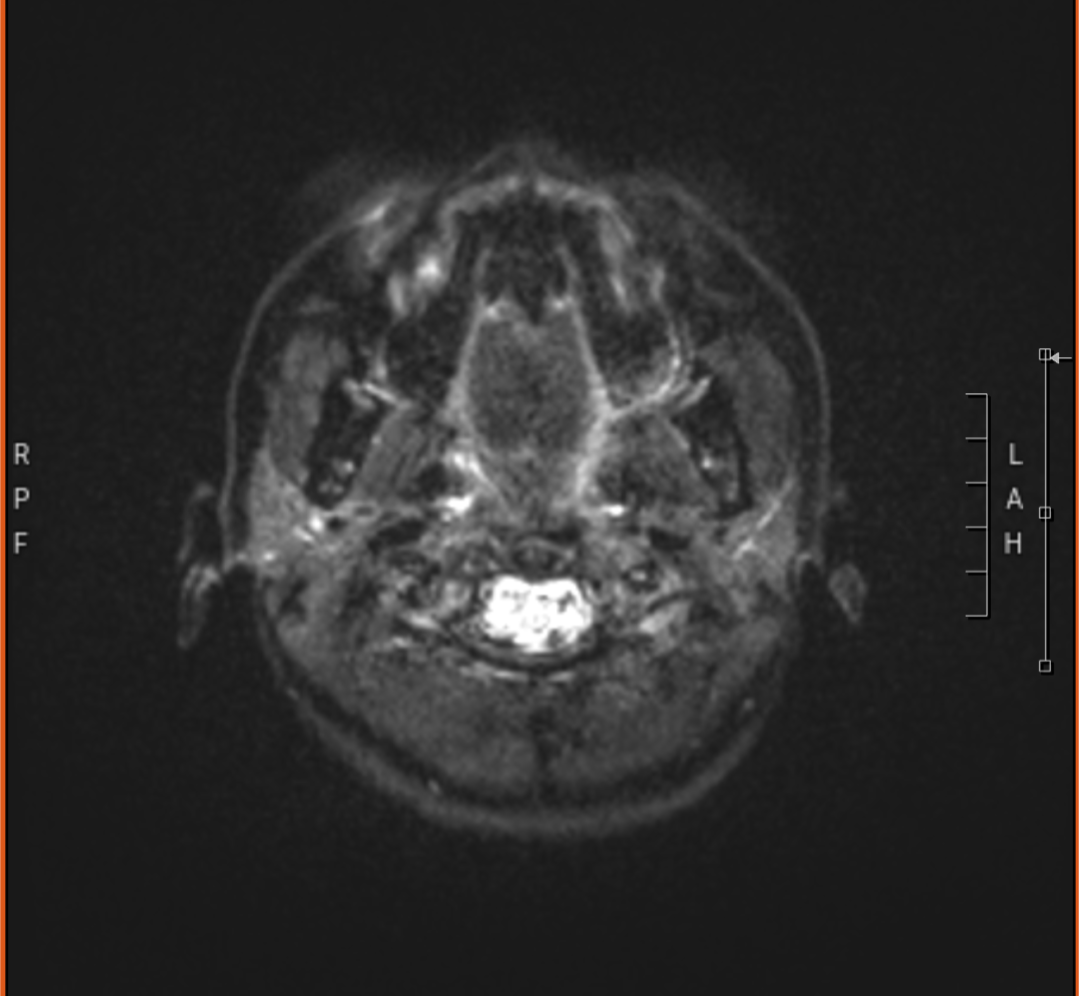

The process of MS diagnosis for me was easier than most. My neurologist didn't do any invasive testing. I didn't need a spinal tap. My symptoms and two MRI scans I had a year apart were what confirmed MS.